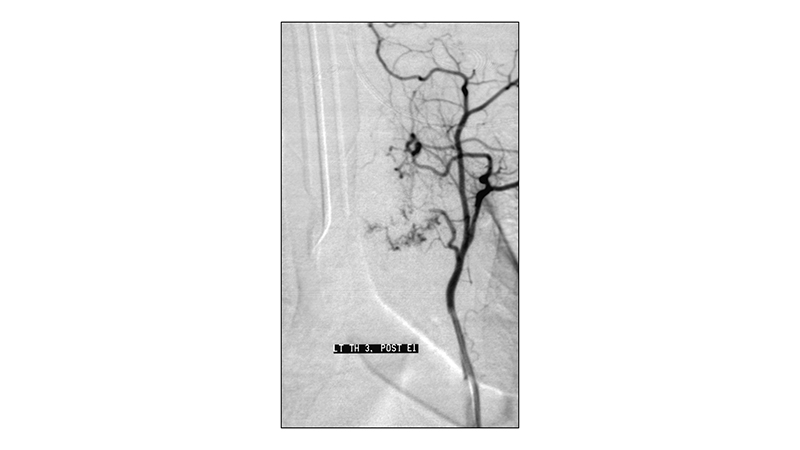

Εικόνα 6: Στην τελική αγγειογραφία της αριστερής Θ3 μεσοπλευρίου αρτηρίας μετά τον εμβολισμό, ελέγχεται η απόφραξη του τροφοφόρου κλάδου. Παραμένει μικρή τριχοειδική αιμάτωση της περιφέρειας του όγκου.

peristatiko aimaggeiwmatos spondulikhs sthlhs.006